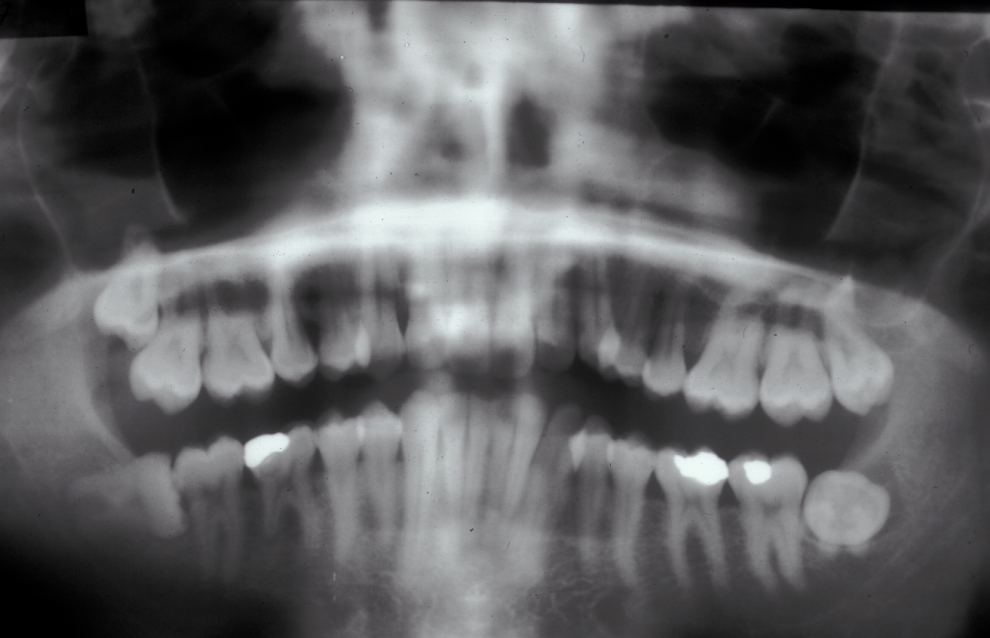

Assessment of the tooth is both clinical and radiographic. If somebody presents in pain, it is important to establish that this is coming from the third molar and not elsewhere. Pain is often vague, poorly localised and may be referred from another tooth, or as part of facial arthromyalgia (condition affecting the jaw joint). A dental panoramic radiograph is ideal as it helps to assess all the teeth at once. The health of the adjacent molars may influence the decision whether to remove the third molar or not. Large crowns or old restorations are all at risk of dislodgement during surgery. It is also worth considering whether alternative treatment options are available. For instance, pericoronitis due to an over-erupted upper third molar may be dealt with by extracting that tooth only, with or without operculectomy. In the presence of other teeth of poor prognosis, will it be better in the long term to save the third molar which may be used as a denture or bridge abutment in the future?

These points help to determine whether the tooth can be simply elevated or will need a surgical approach. A series of radiographs depicted in Figure 4 to Figure 8 illustrate these points further.